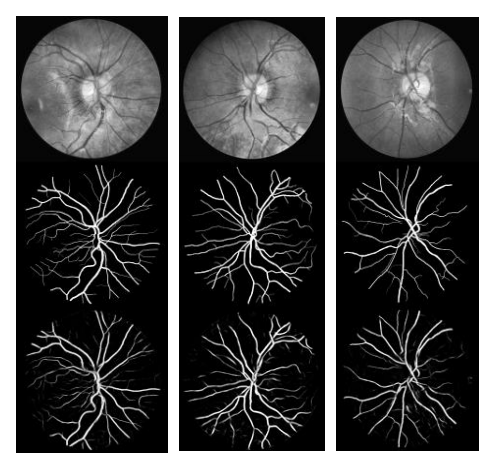

3) CHASE_DB1

对于定性分析,R2U-Net的示例输出如图14所示。对于定量分析,结果如表1所示。从表中可以得出结论,在所有情况下,所提出的RU-Net和R2U-Net模型在AUC和准确性方面都表现出更好的性能。图15显示了三个视网膜血管分割数据集上R2U网络模型的最高AUC的ROC。

为了证明RU-Net和R2U-Net模型的性能,我们在三个不同的医学影像数据集上对它们进行了测试。这些包括从视网膜图像中分割血管(如图6所示的DRIVE、STARE和CHASE_DB1)、皮肤癌病灶分割和2D图像中的肺分割。对于这个实现,Keras和TensorFlow框架在一台拥有56G RAM和NIVIDIA GEFORCE GTX-980 Ti的GPU机器上进行实验。

另一种方法是“leave-one-out”方法,即对每个图像进行测试,并对剩余的19个样本进行训练[47]。因此,训练和测试之间没有重叠。在这个实现中,我们对STARE数据集使用了“leave-one-out”方法。CHASH_DB1数据集包含28个彩色视网膜图像,每个图像的大小为999×960像素[48]。该数据集中的图像采集自14名学龄儿童的左右眼。数据集被分成两组,其中样本是随机选择的。20个样本集用于培训,其余8个样本用于测试。